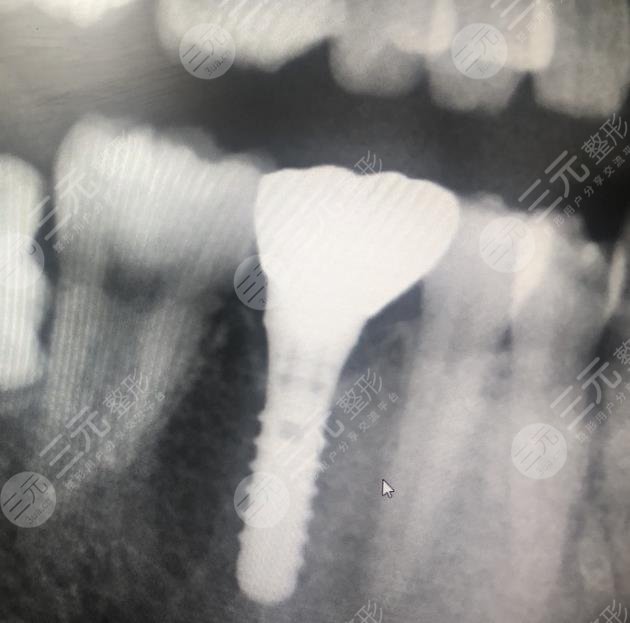

二、杭州美奥口腔医院种植牙案例分享

我的牙齿是因为一次过年吃甘蔗的时候不小心给搞掉了的,后来一直也没有补它,但是近来因为没有管它,导致有食物残留进入了牙缝使得牙齿发炎的了,到了医院进行检查后,医生告诉建议我做种植牙,把这颗牙补上,如果不补的话,对于牙齿是很不好的,所以我就决定了做种植牙手术。

整个手术的过程是比较久的,因为中间有一个恢复的过程,比较麻烦的就是种植体的安装,这个过了后面就好了很多,现在我的牙齿已经种好了,这颗牙和之前的牙差别也不是很大,并且用起来也是非常舒服的,没有什么不适的感觉,整体是很棒的。